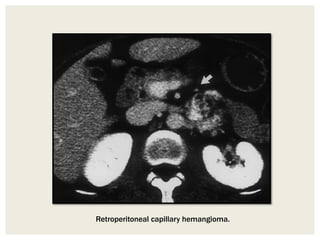

Retroperitoneal capillary hemangioma.